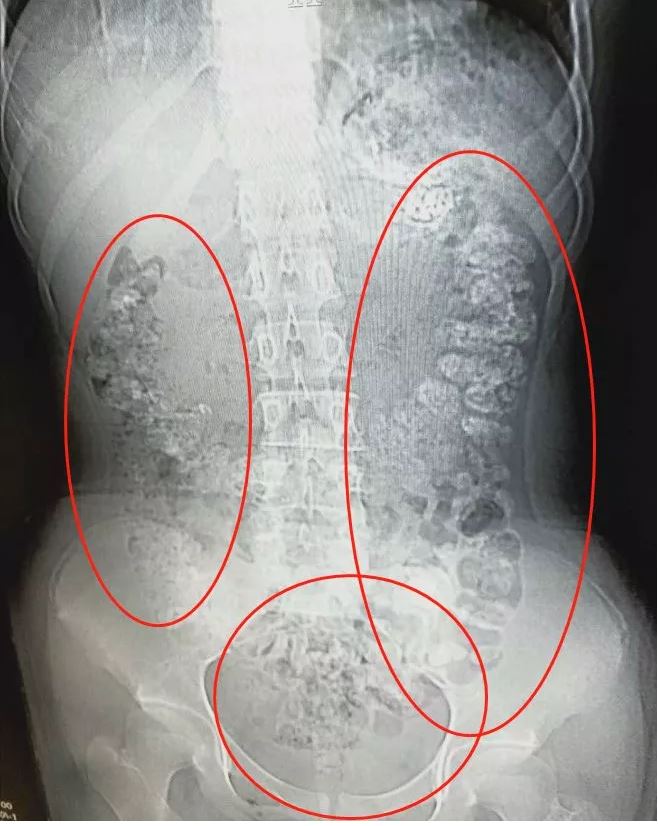

14岁女孩喝了珍珠奶茶后,

五天没有排便,

还肚子疼,

CT检查发现胃肠道

布满一颗颗圆圆的高密度阴影

肠胃道里全是“珍珠”

近日,诸暨市人民医院急诊科晚上9点收治了一名14岁小姑娘朱丽(化名)。她说自己肚子疼,已经四五天没有排便了。

急诊科医生张楼炜对朱丽进行了初步检查,发现她肚子鼓鼓的,就让她去做了腹部CT,谁知道,拍出来的片子让张楼炜大吃一惊,患者胃部、横结肠、升结肠、降结肠、乙状结肠,一直到肛门,全是颗粒状阴影,足有百余颗。

张楼炜问小沈最近吃过什么不易消化的食物?女孩吞吞吐吐地说5天前喝过珍珠奶茶。

“小女孩可能是怕父母说她,而隐瞒了——这么多未消化的‘珍珠’不像喝一杯奶茶就积累的,应该是近期喝了一段时间造成的。”张楼炜推断。之后,他给患者开了润肠通便的药物,帮助将未消化的“珍珠”排出体外。

珍珠奶茶里的“珍珠”是用木薯淀粉做的,本身就不易消化。再加上商家为了令“珍珠”更Q弹、有嚼头,就会在制作过程中加入一些胶类的物质,令珍珠难以消化。